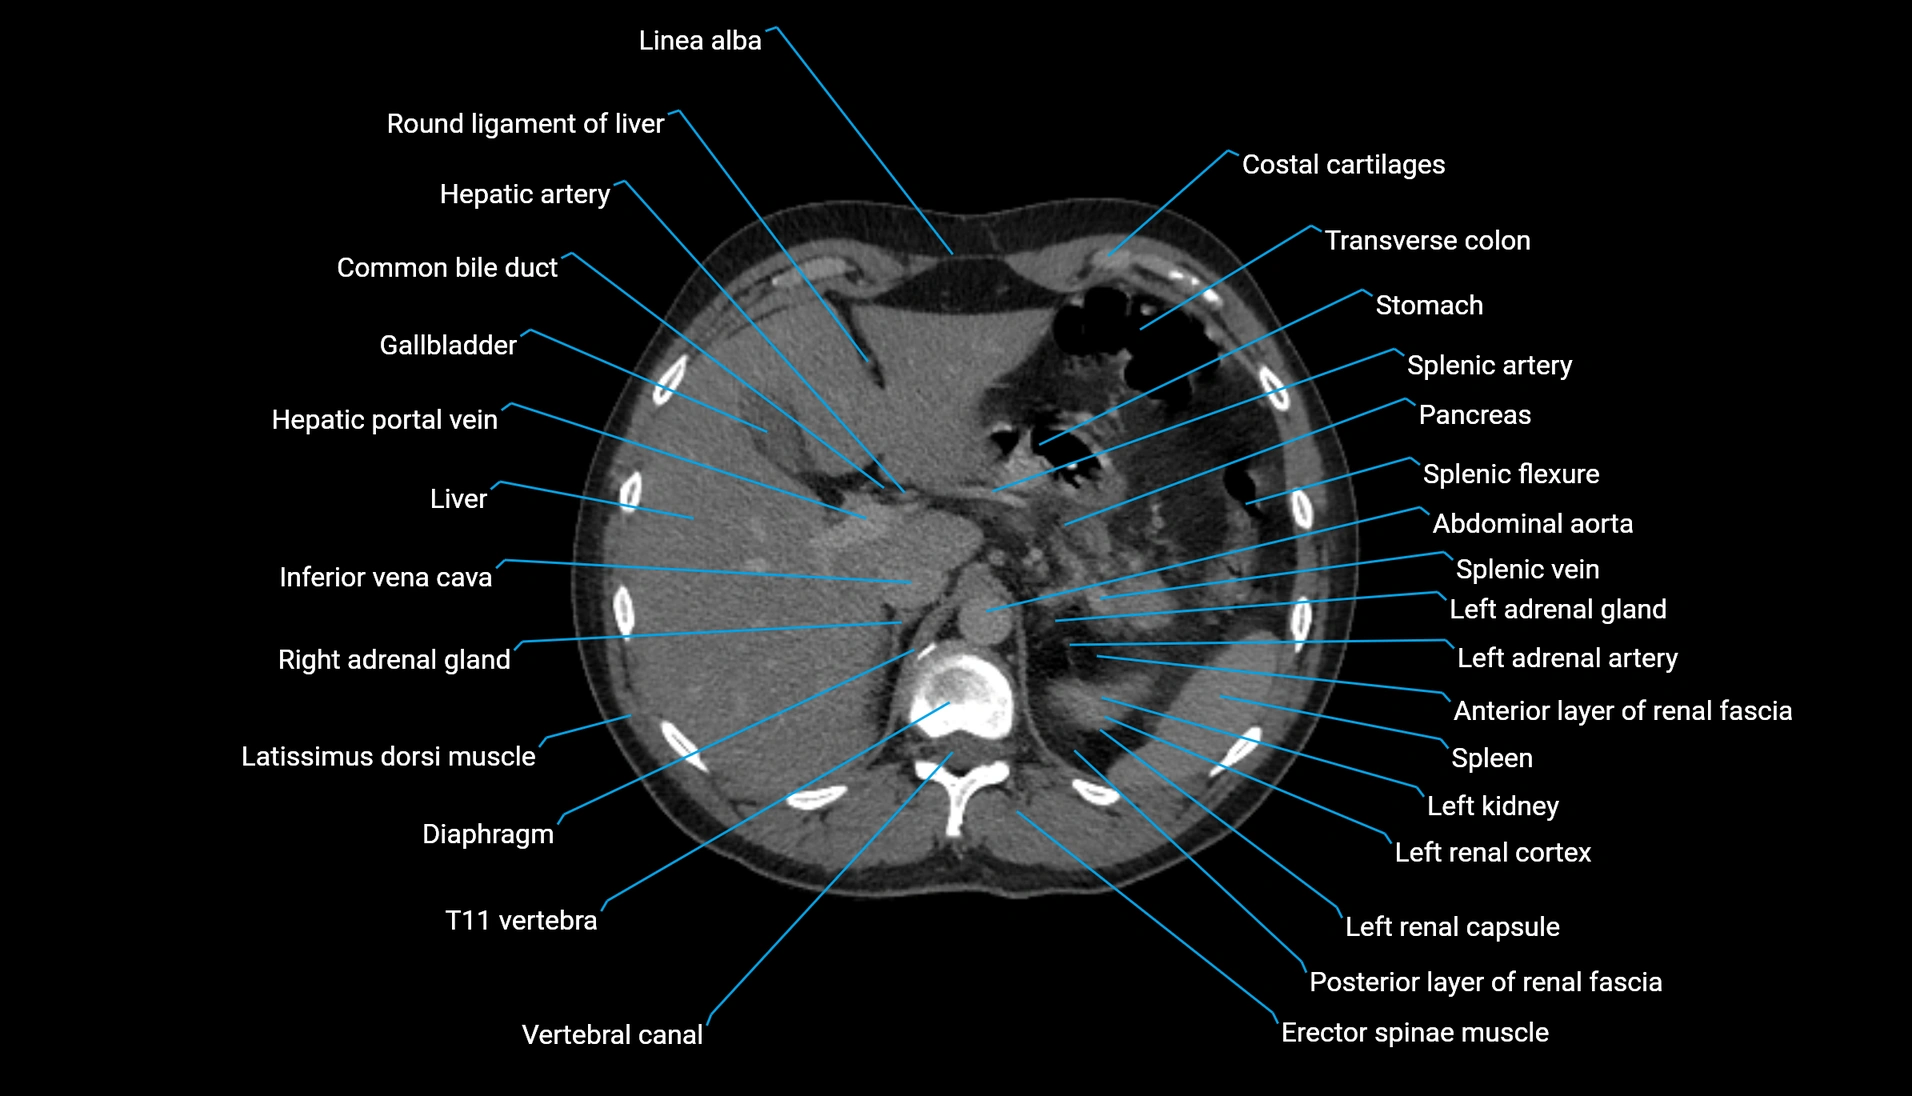

CT Appearance

Non-contrast CT:

-

Demonstrates cortical bone of acetabular rim in excellent detail

Detects fractures, dysplasia, retroversion, or bony overcoverage (pincer impingement)

3D reconstructions used in preoperative hip surgery planning

CT image